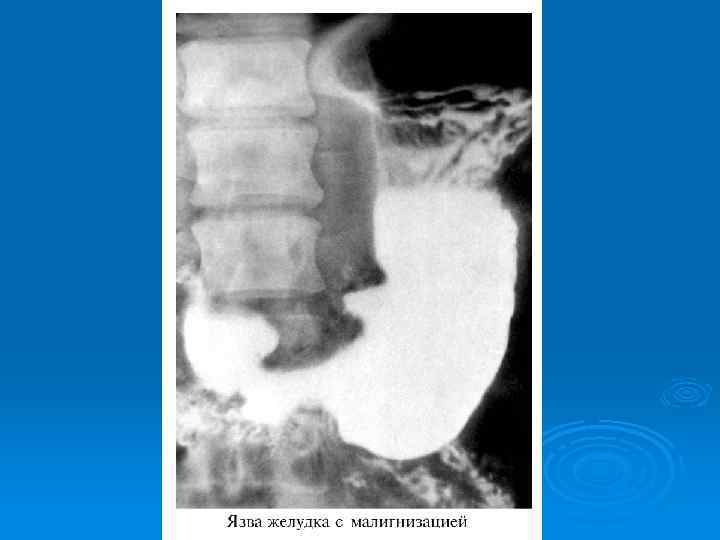

МАЛИГНИЗАЦИЯ Ø Перерождение в рак является возможным осложнение язв желудка в 15 20% случаев Ø Язвы 12 п. к. не малигнизируются Ø Лечение при угрозе малигнизации хирургическое

Показания к хирургическому лечению Ø Если проводимое лечение в течение 3 лет ежегодно не менее 2 курсов длительностью 3 месяца неэффективно Ø Угроза малигнизации